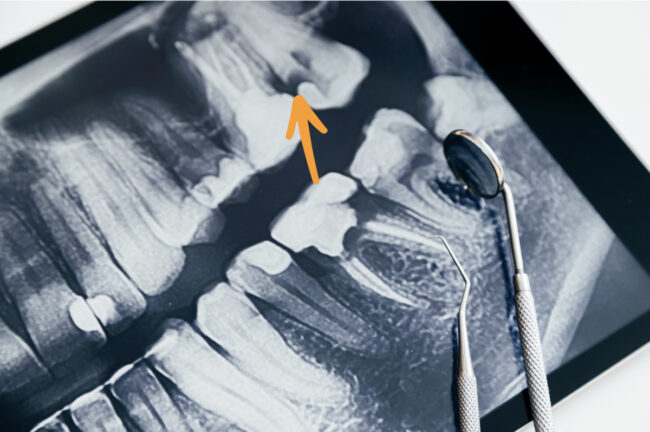

Raspado y alisado radicular: qué es y cómo saber si lo necesito

Es muy común que muchos pacientes acudan a nuestra clínica dental en Madrid, en la calle San Bernardo, solicitando una «limpieza bucal normal» y, tras una exploración detallada por nuestros odontólogos, descubramos que necesitan un tratamiento más profundo para eliminar los restos de placa y devolver la salud a sus dientes y encías. Es en…